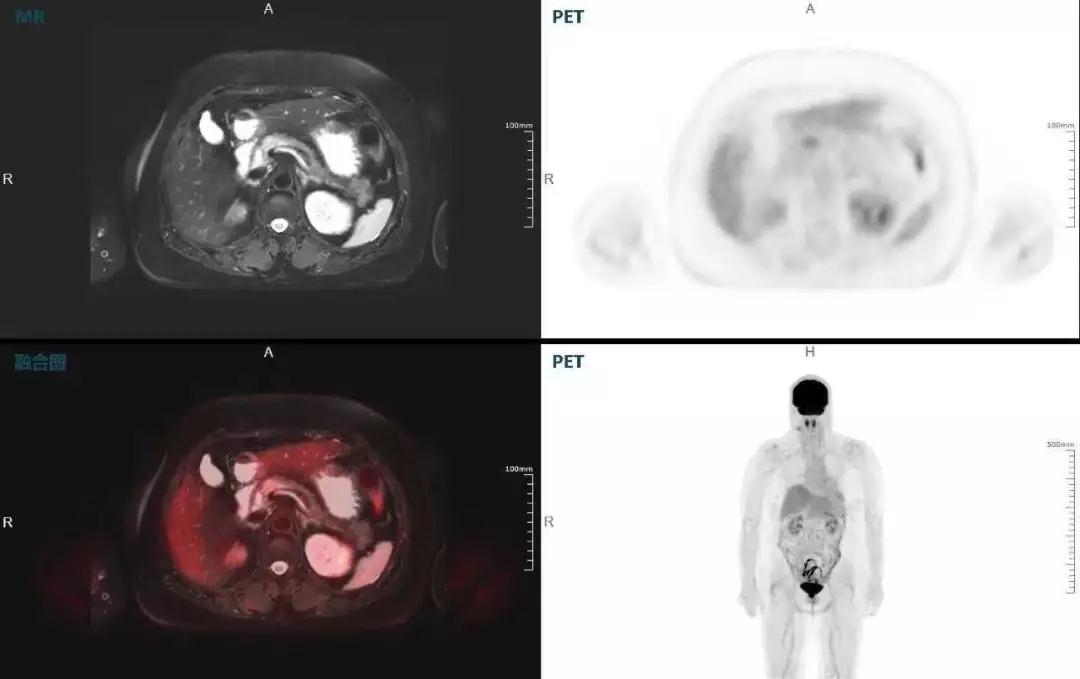

中山醫(yī)院核醫(yī)學(xué)科在臨床實(shí)踐中發(fā)現(xiàn),基于聯(lián)影“時(shí)空一體”超清TOF PET/MR,不僅解剖信息和代謝信息能夠完美融合呈現(xiàn),同時(shí)精細(xì)展示局部病灶與周圍組織的復(fù)雜關(guān)系,并能全盤檢測(cè)病灶的全身轉(zhuǎn)移,為醫(yī)生臨床診斷提供更豐富信息。

(胰腺腫瘤,MR顯示胰腺體部信號(hào)異常,PET顯示稍高攝取,結(jié)構(gòu)改變和功能異常提示胰腺M(fèi)T可能大。)